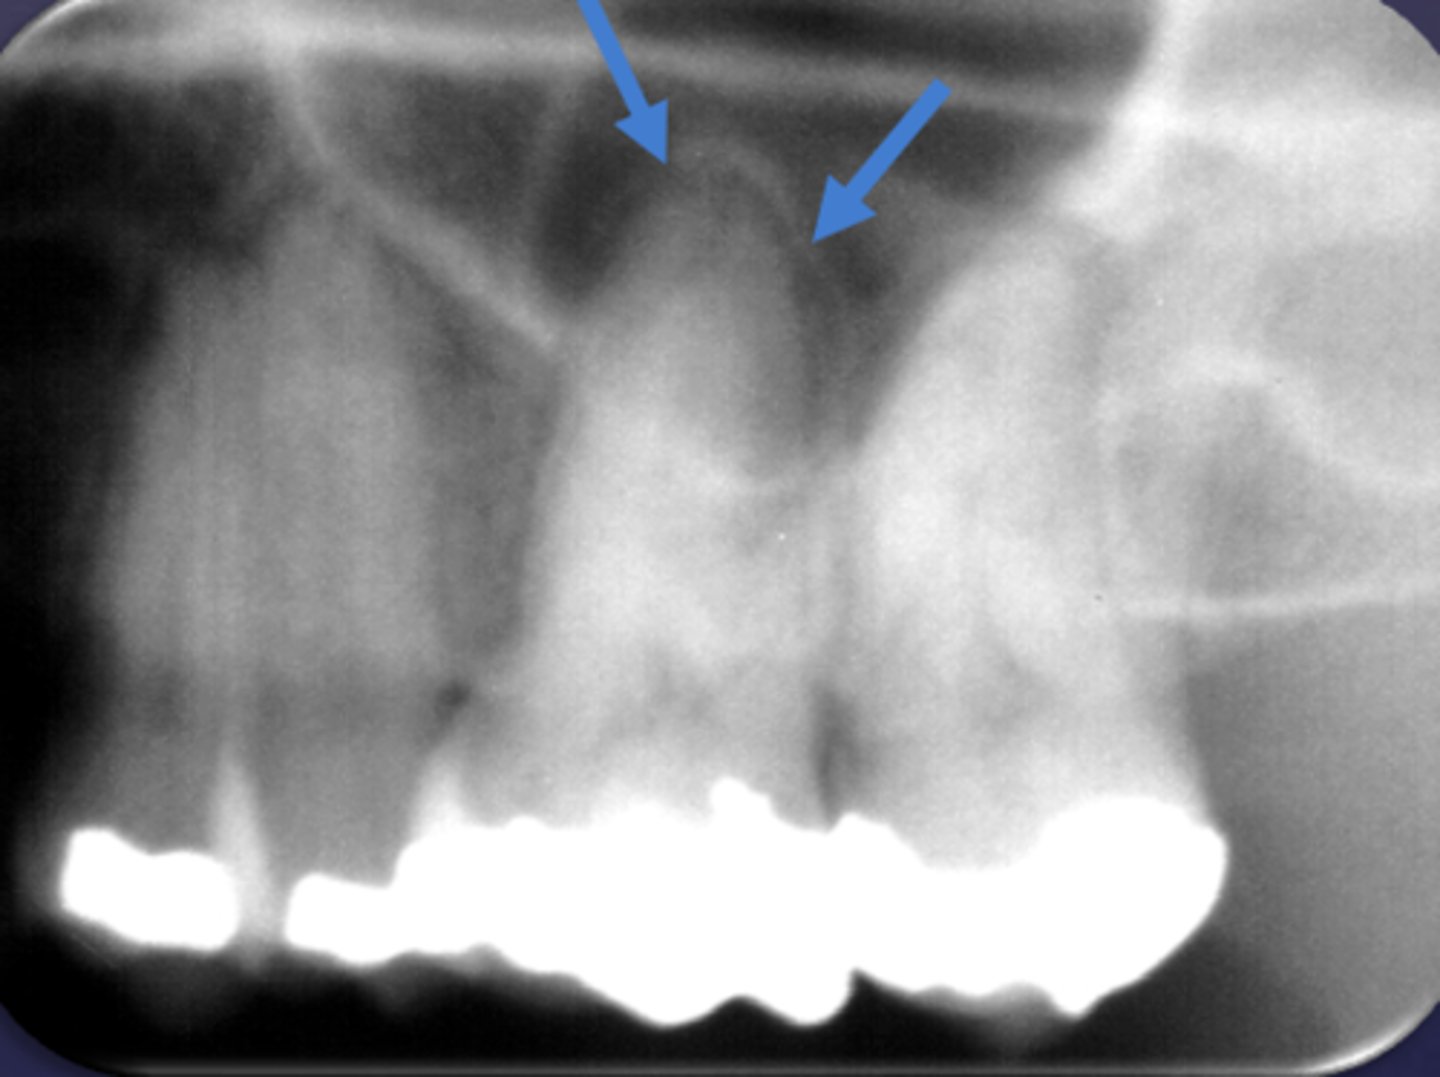

What are two defects that the arrows are pointing to?

- Widened PDL

- Sclerosis

What type of change is seen in this radiograph?

early change (apical periodontitis #17-18)